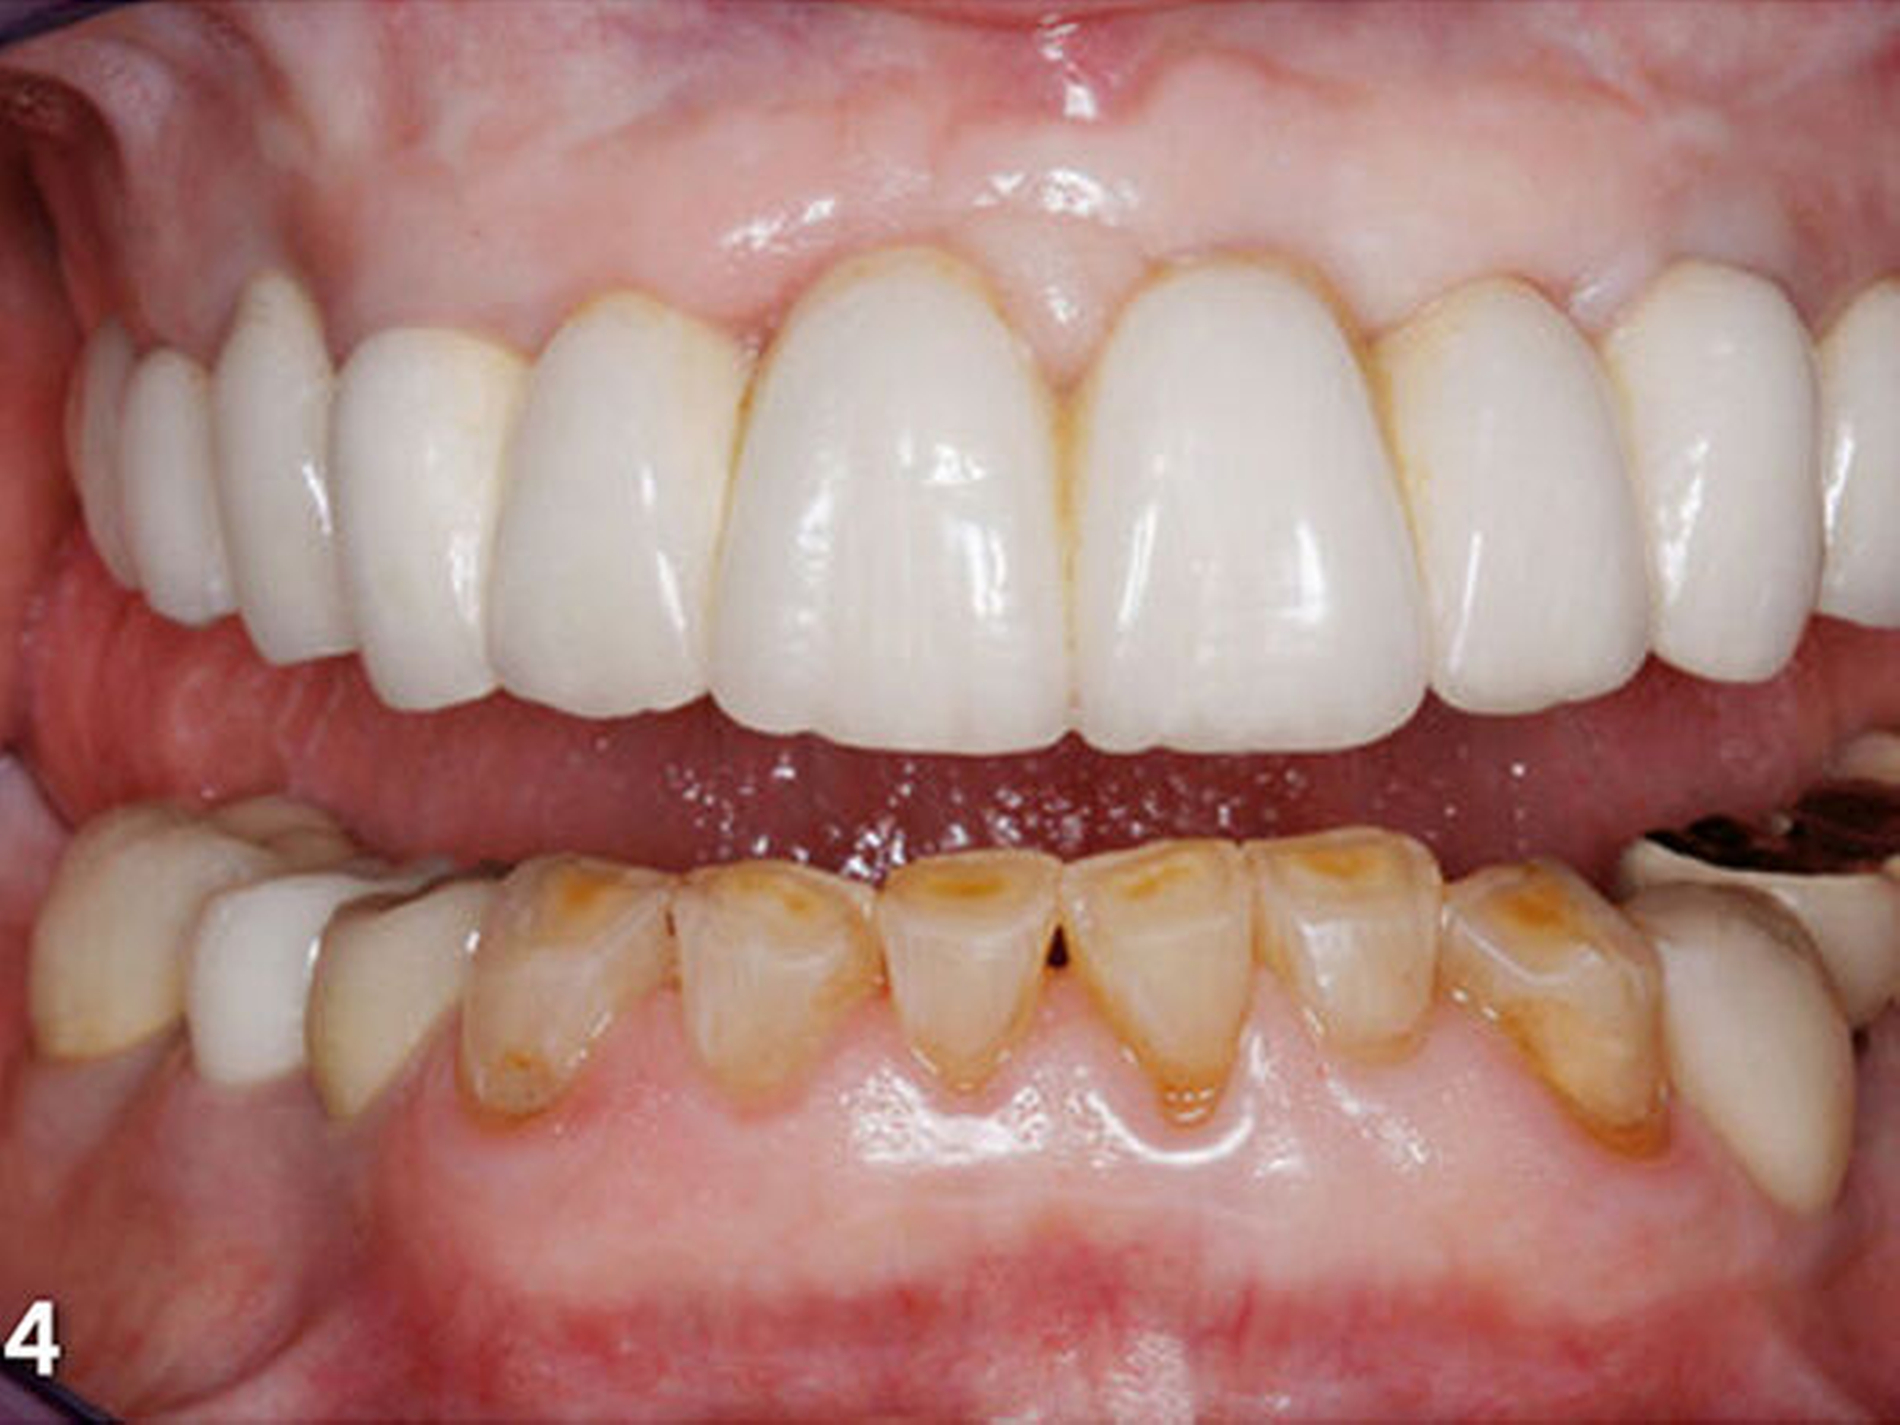

Die Patientin wies deutliche Zeichen von Attrition und Abrasion an den Unterkieferfrontzähnen (Abb.2) und ein Defizit in der vertikalen Distanz der Okklusion auf (Abb.3). Im Unterkieferfrontzahnsegment war eine kompensatorische Eruption des Kieferkamms in Richtung Okklusionsebene eingetreten, die verbreiterte keratinisierte Gingiva gibt darauf einen deutlichen Hinweis (Abb.4) (Bartlett & Smith 2000; Berry & Poole 1976; Cekic Nagas &Ergun2015; Manfredini & Poggio 2016).